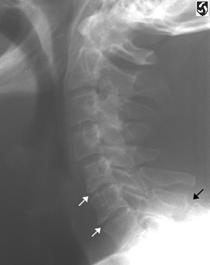

Fractura spanzuratului Fractura anterioara C4 Fractura C5 in lacrima in flexie

"in lacrima"

![]()

Fractura C5 "in lacrima" in extensie Luxatie fatetara

unilaterala Luxatie

fatetara bilaterala

C5 - C6 C5 - C6

Incidenta laterala Fractura Clay-Shoveler Luxatie atlanto-occipitala si